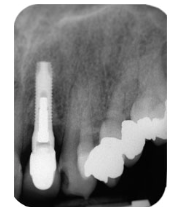

而且也要用牙线,虽然种的牙不会龋坏但它旁边的牙是可能龋坏的,像这样↓

怎么选洁牙器械假牙又不会蛀牙,洗个牙怎么那么贵_https://www.jmylbn.com_新闻资讯_第6张

怎么选洁牙器械假牙又不会蛀牙,洗个牙怎么那么贵_https://www.jmylbn.com_新闻资讯_第7张